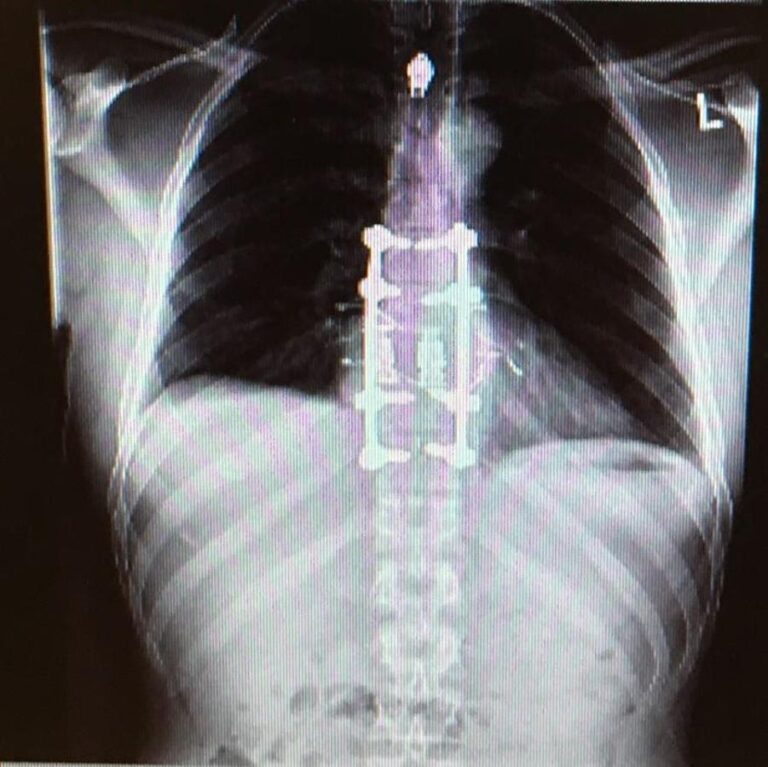

A tumor was growing in my 9th vertebrae, it cracked my spine, and was days away from attaching itself to my spinal cord which would have likely resulted in paralysis from the waist down. I had to have surgery in early January 2016 called an en bloc resection, to remove the tumor and part of my spine and replace it with metal rods and screws that are still in my back today.

spinal fusion 2016